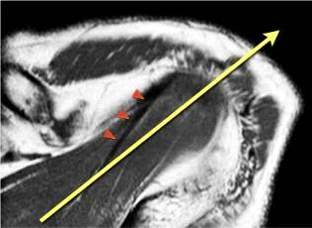

Подвергаясь тендинопатии и повреждению, сухожилие

надостной мышцы является важнейшей частью ротаторной манжеты. Повреждения

сухожилия надостной мышцы лучше видны в косой корональной плоскости и в

положении отведения и поворота плеча кнаружи (ABER - abduction external

rotation). В большинстве случаев ось сухожилия надостной мышцы (головки

стрелок) отклонена кпереди от оси мышцы (желтая стрелка). При планировании

косой корональной проекции лучше ориентироватьия на ось сухожилия надостной

мышцы.